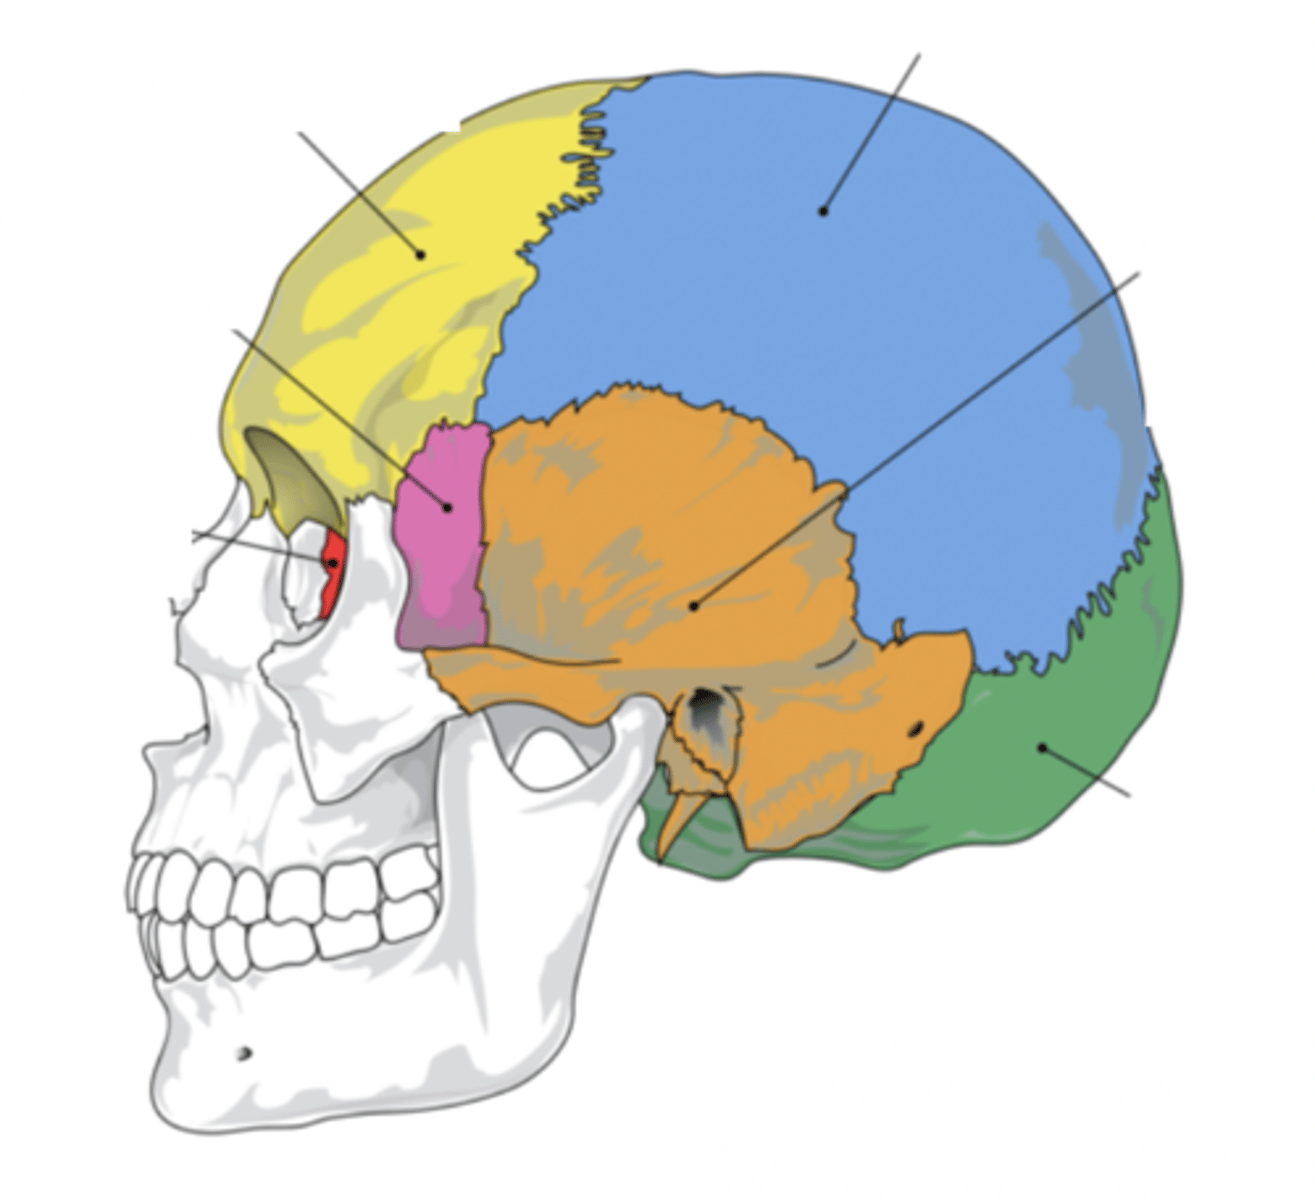

Cranial Bones (8)

- Ethmoid

- Frontal

- Sphenoid

- Temporal (2)

- Occipital

- Parietal (2)

(EFSTOP)

Ethmoid Bone

Forms part of the posterior portion of the nose, the orbit, and the floor of the cranium (red)

Frontal Bone

Bone that forms the forehead (yellow)

Sphenoid Bone

Forms part of the base of the skull and parts of the floor and sides of the orbit (pink)

Temporal Bone (2)

Bone that forms parts of the side of the skull and floor of the cranial activity (orange)

Occipital Bone

Bone that forms the back of the head (green)

Parietal Bone (2)

Either of two skull bones between the frontal and occipital bones and forming the top and sides of the cranium (blue)